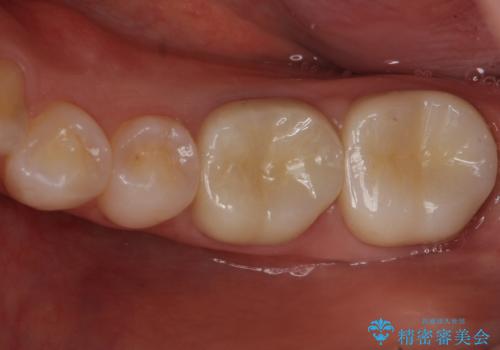

変色した樹脂の詰め物 セラミックでのやり替え

奥歯が樹脂の詰め物で継ぎ接ぎになっていることが確認されたため、今後の虫歯リスクを減らすために適合の良いフルジルコニアクラウンを入れていきます。

- 左下67 仮歯+フルジルコニアクラウン 22,000円+154,000円費用は治療当時の料金となります

樹脂をすべて取り、虫歯も取り切った後に適合の良いクラウンを装着することで今後の虫歯リスクを減らすことができます。